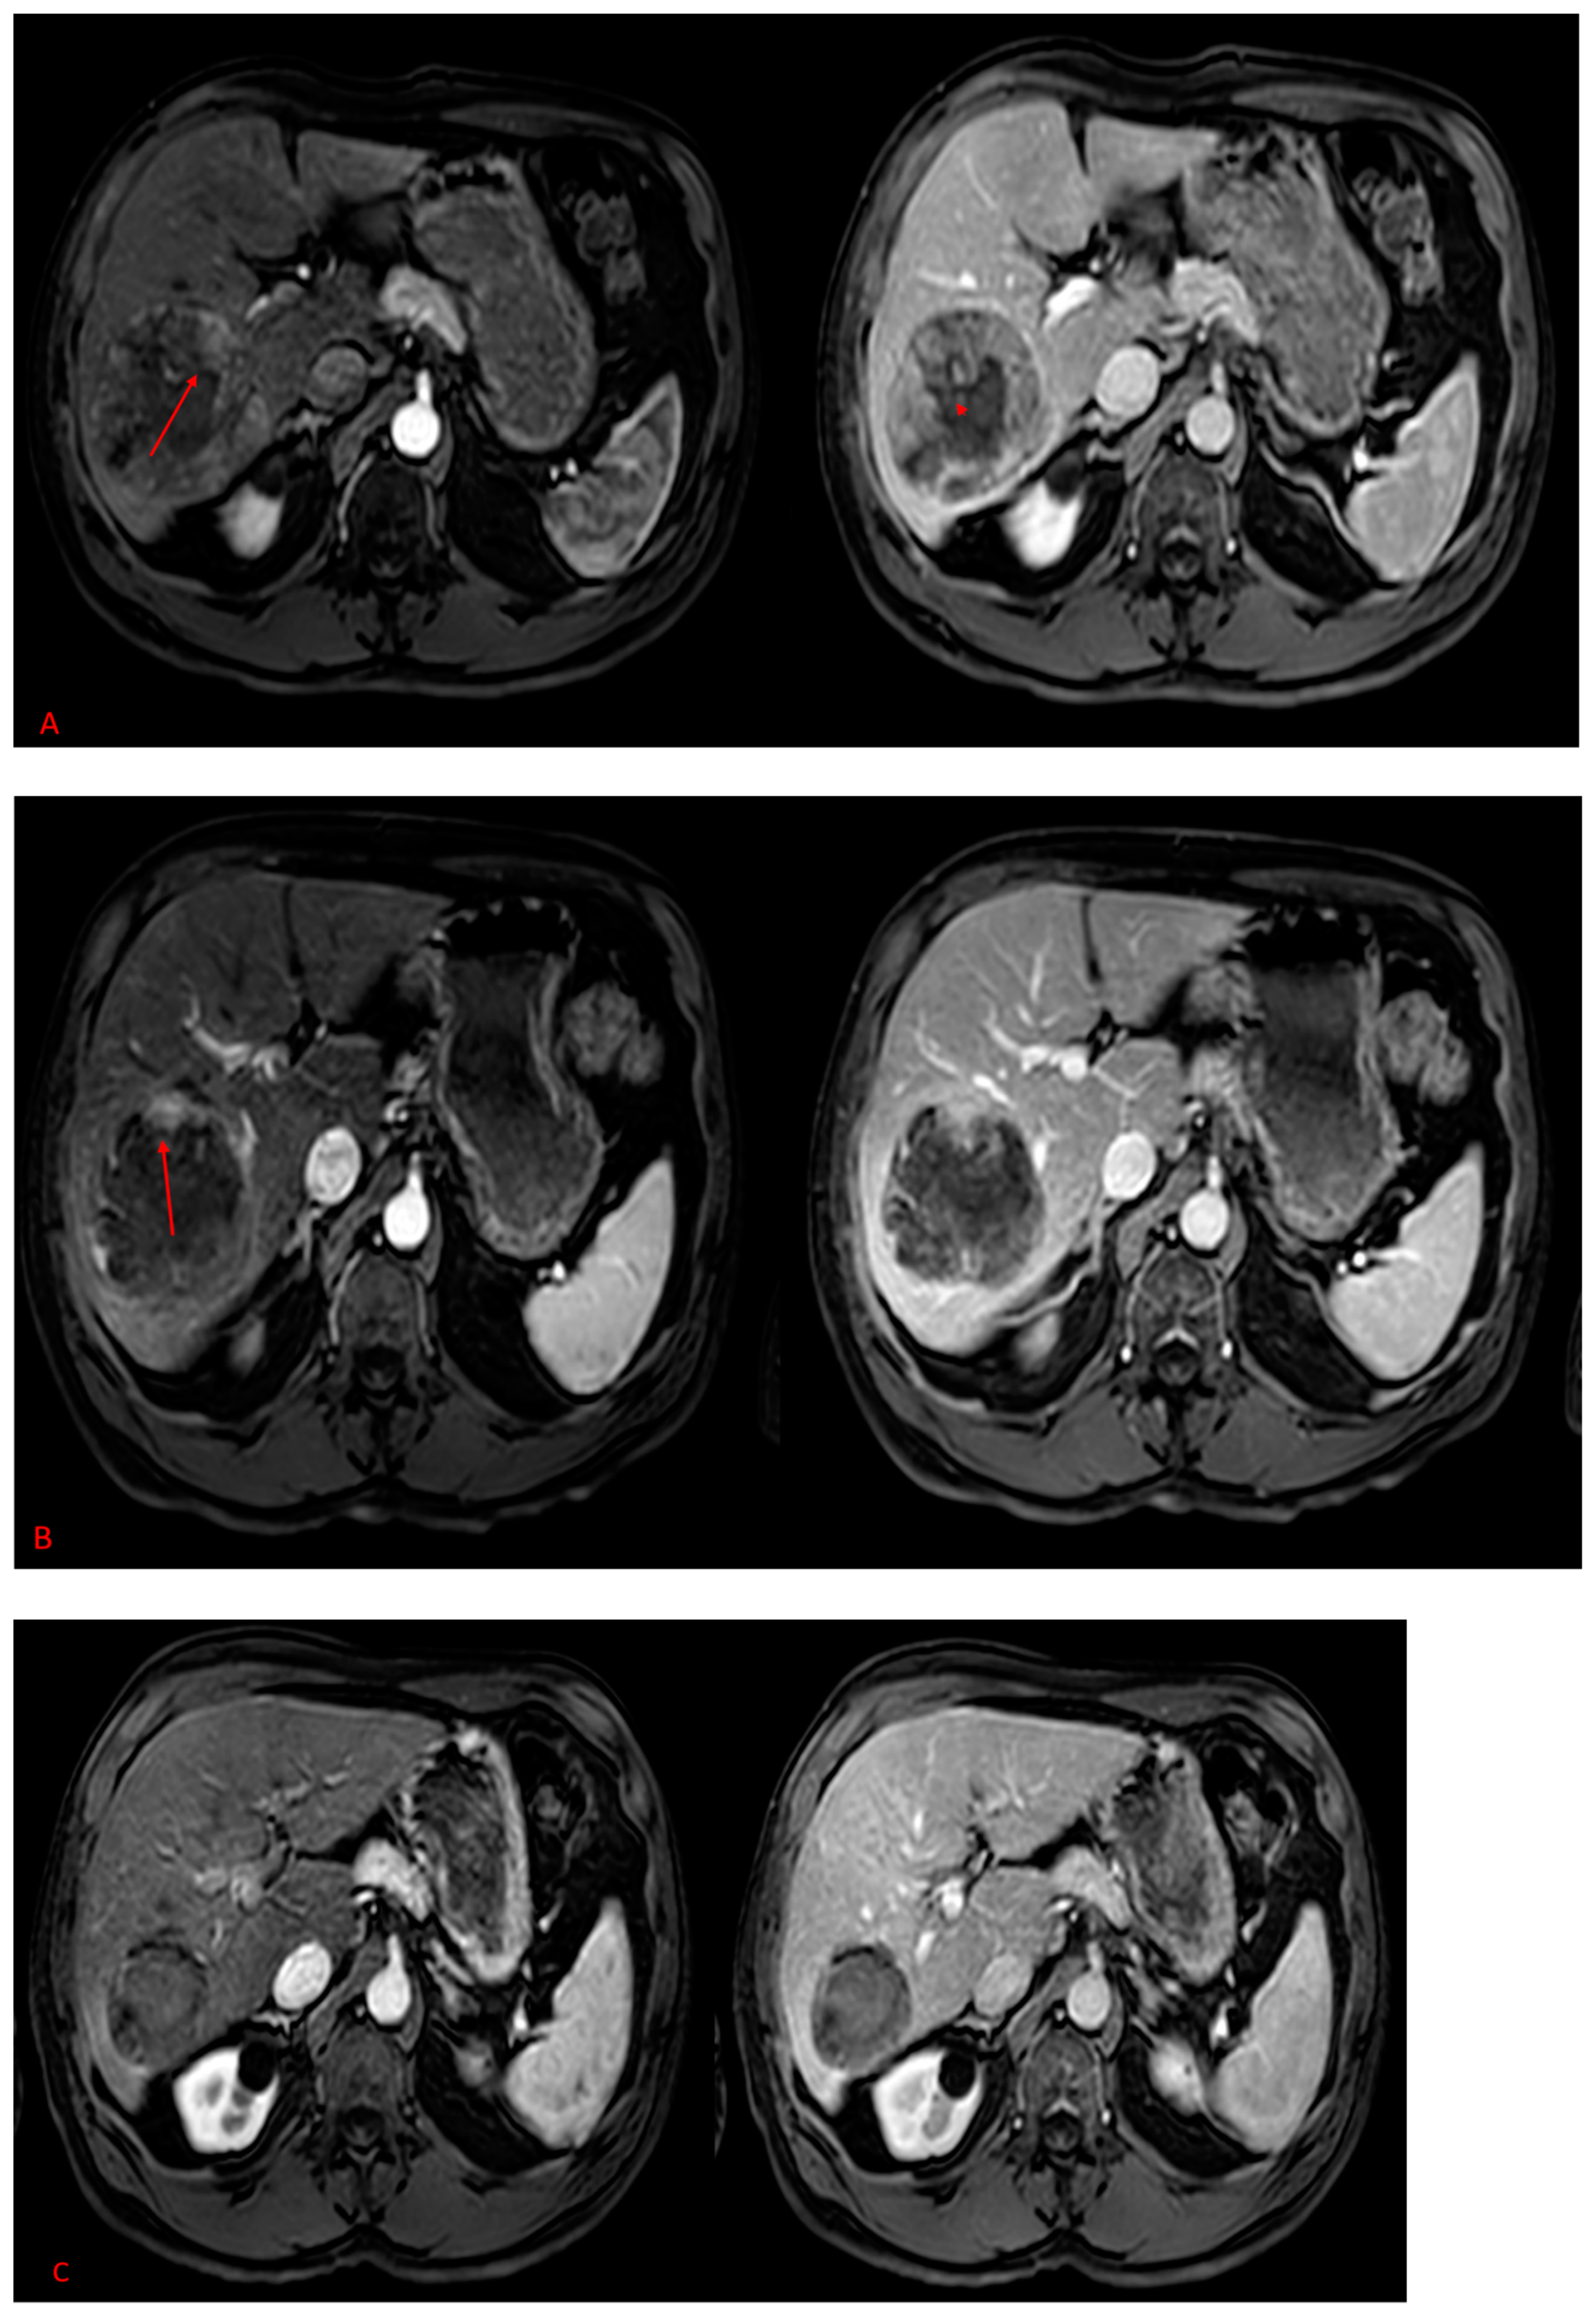

2. Results

2.2. MAA-Based Dosimetry Analysis

2.3. 90Y-Based Dosimetry Analysis